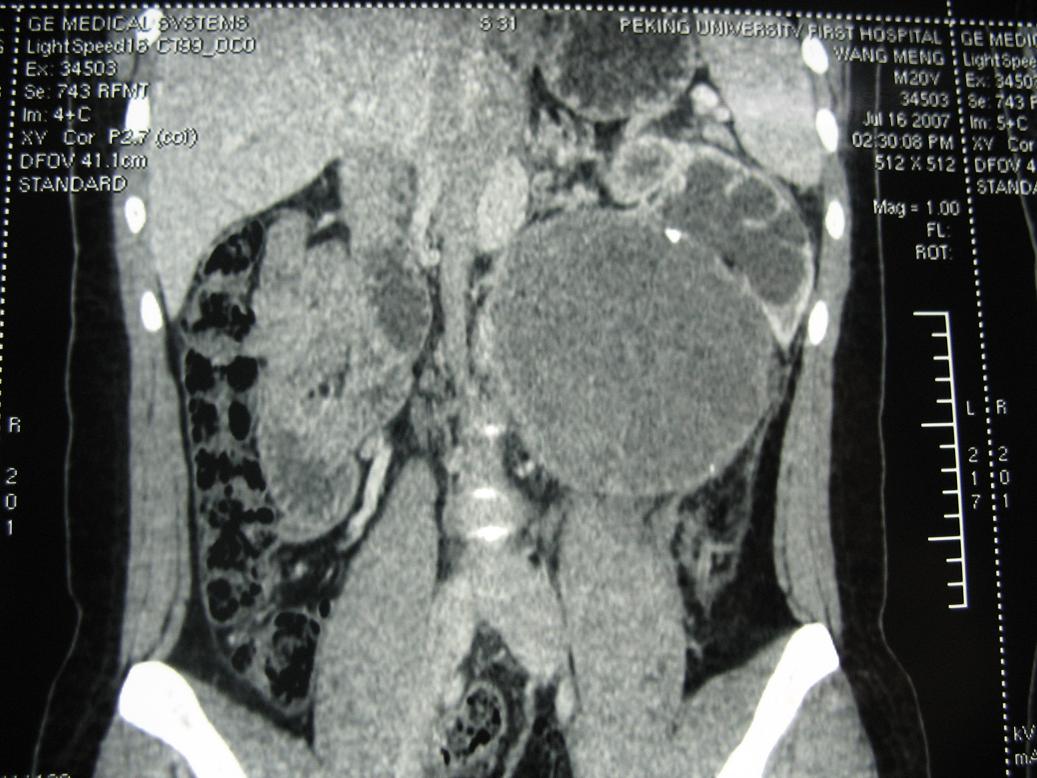

2、左侧腹膜后囊实性占位性病变,有完整包膜,周围脏器及血管呈受压移位改变,左肾积水,肾实质变薄,增强扫描示病变包膜有强化,因图片太少,实性部分是否强化不好判断。

3、诊断:结合病人年龄,左肾改变考肿虑为输尿管受压肾积水时间长,左肾实质萎缩,病变未见明显外侵征象,本人首先考虑为神经源性瘤囊变可能性大。

结果收到,肿块较大,密度不均,实性部分有强化,包绕腹主动脉推挤左肾,左肾集合系统受压改变,病灶长轴与腹主动脉平行,支持副神经节瘤,但不典型。